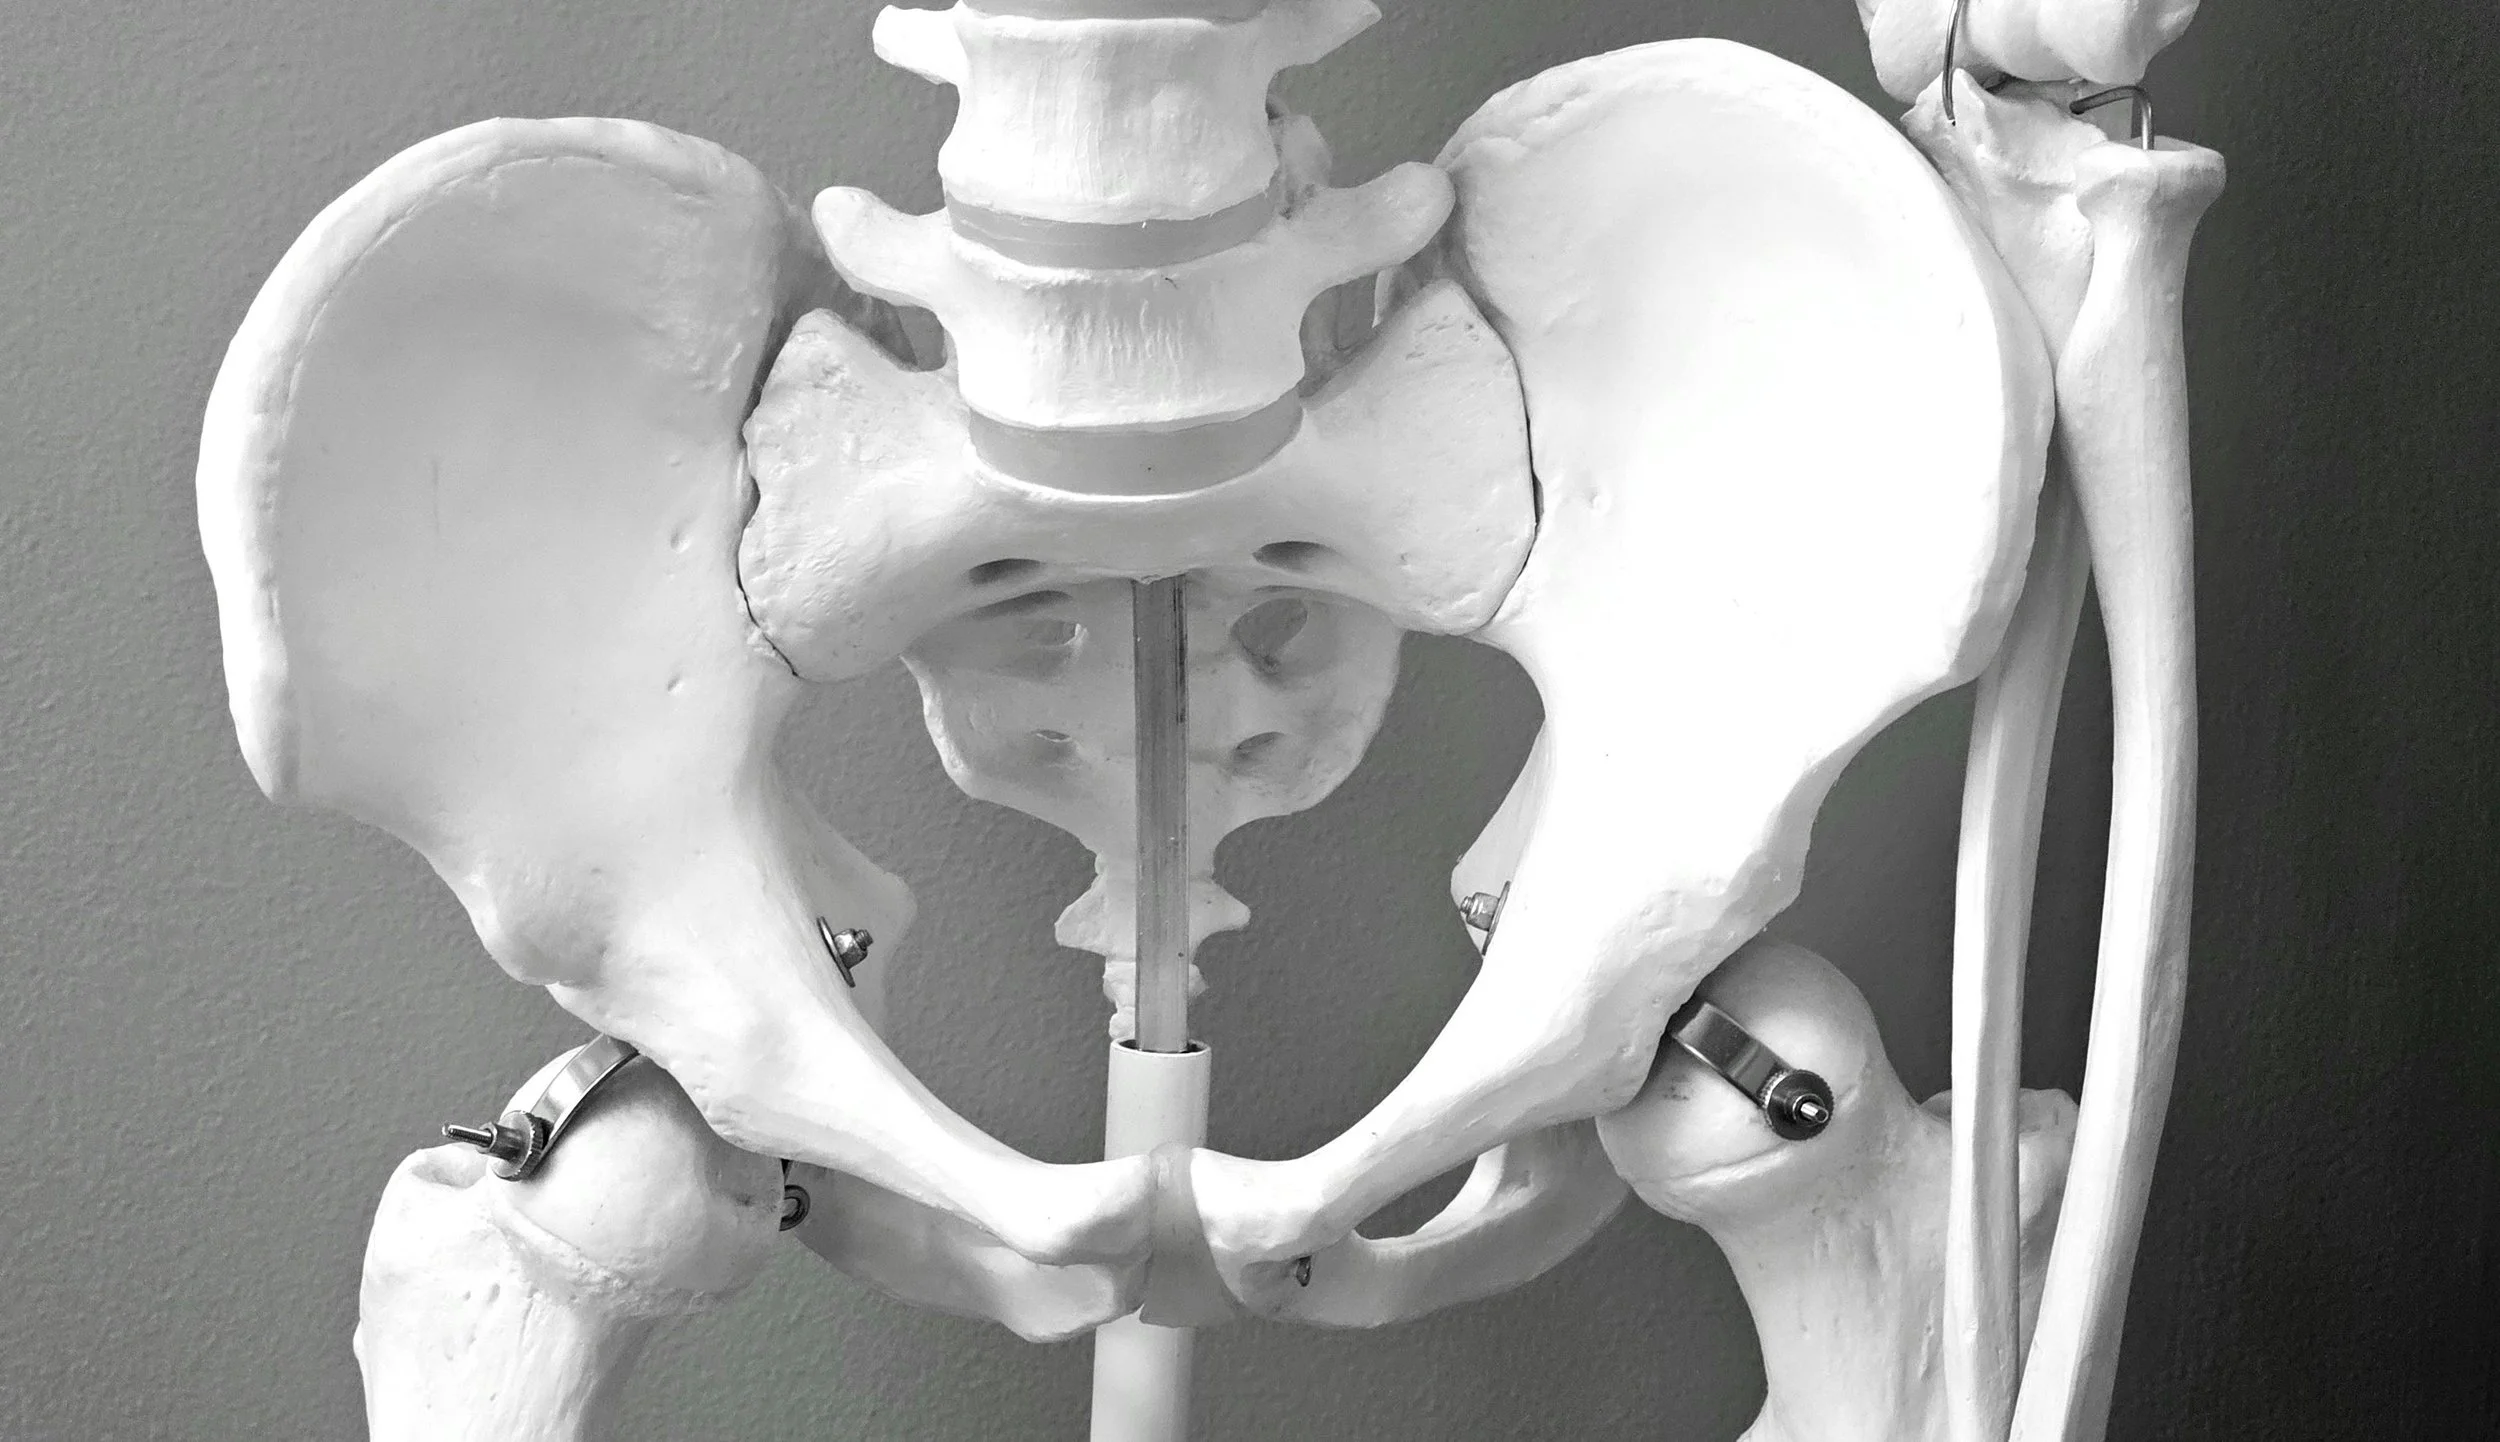

Pelvic Floor Health: Why It Matters and How Acupuncture Can Help

Pelvic floor dysfunction can cause pelvic pain, urinary issues, and discomfort. Learn how acupuncture and Traditional Chinese Medicine can support pelvic floor health naturally.

Pelvic floor dysfunction can cause pelvic pain, urinary issues, and discomfort. Learn how acupuncture and Traditional Chinese Medicine can support pelvic floor health naturally.